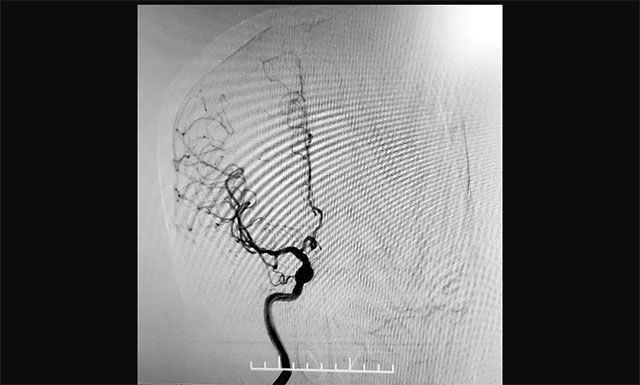

2020年12月22日,75岁的患者吴女士(化名)因“头晕头胀1月余,加重1天”入院。头颅CTA:双侧颈内动脉C4-6段钙化斑形成,伴相应管腔轻度狭窄;双侧大脑前动脉A2段、大脑中动脉远端分支、双侧大脑后动脉P2-3段多发局灶性轻-中狭窄。为做鉴别诊断并了解脑血管情况,有必要进行脑血管造影检查进行评估。

考虑到患者年龄较大,不适宜长时间卧床,张琪博士遂决定经桡动脉入路行全脑血管造影术。经过详细的术前准备,2020年12月26日,张琪博士带领介入团队成功为患者进行了手术,术程顺利,耗时约30分钟,术后予桡动脉压迫器压迫术口,术后护理简单,不影响康复治疗,无术后制动,获得病人及家属的一致好评。